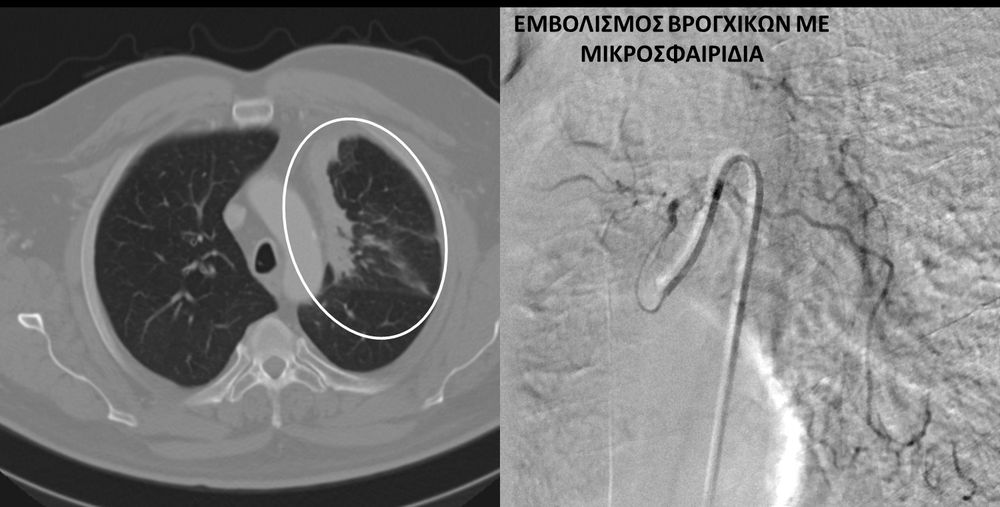

Υποτροπιάζουσα αιμόπτυση

Συνοπτικά υπό την καθοδήγηση του αγγειογράφου, αναγνωρίζεταιτο παθολογικό αγγείο-αγγεία και με ειδικούς καθετήρες και μικροκαθετήρες, διοχετεύονται εμβολικά υλικάόπως μικροσφαιρίδια ή coils, ώστε να αποφραχθεί ή να μειωθεί η παθολογική αγγείωση.